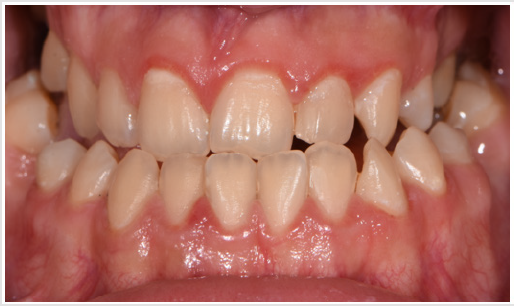

A female patient presented in our office for a consult. Her oral hygiene status needed improvement especially in the frontal upper area. Intraoral photographs reveal that in the transversal plane she had crossbite contacts between all the teeth and severe discrepancy between and the midline of the face the upper arch midline which was deviated to the right with almost the size of a lower incisor. In the sagittal plane she had canine class III on the right side and class I on the left side due to the rotated mandibular left canine and end to end to inverse overjet in the anterior region (Figures 3 & 4) and in the vertical plane, she had 1 to 2 mm of inverse overbite and bilateral open bite. Her upper right maxillary molars were absent and she presented moderate crowding in both upper and lower arch. The steps in the treatment plan were to expand the maxilla with the aid of a Hybrid Maxillary Expander followed by fixed appliances on the both Arches. In this case report, we present the results after the expansion of the maxilla and the processes that needed to be followed for the fabrication of the Hybrid Maxillary Expander. The first steps in the digital planning were clinical examination and intraoral scanning. The patient was referred to a radiological center for a CBCT. The intraoral scan and the CBCT were sent to the laboratory and analyzed for the implant planning. The mini screws were planned to be inserted in the anterior part of the palate, paramedian, this being an optimal area that has lower variability of bone thickness, a thinner mucosal layer and a lower density of blood vessels compared to the other [9].